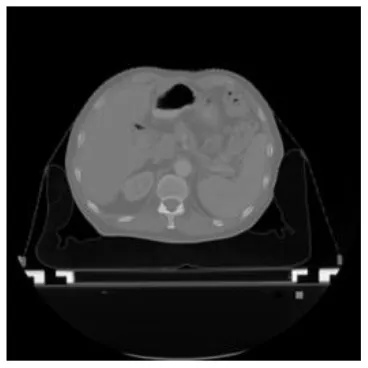

| Input CT image | Organs with manual segmentation | Organ with automatic segmentation | |

| Bladder | ![]() | ![]() | ![]() |

| Brainstem | ![]() | ![]() | ![]() |

| Eye-L | ![]() | ![]() | ![]() |

| Eye-R | ![]() | ![]() | ![]() |

| Femur-L | ![]() | ![]() | ![]() |

| Femur-R | ![]() | ![]() | ![]() |

| Heart | ![]() | ![]() | ![]() |

| Intestine | ![]() | ![]() | ![]() |

| Kidney-L | ![]() | ![]() | ![]() |

| Kidney-R | ![]() | ![]() | ![]() |

| Liver | ![]() | ![]() | ![]() |

| Lung-L | ![]() | ![]() | ![]() |

| Lung-R | ![]() | ![]() | ![]() |

| Mandible | ![]() | ![]() | ![]() |

| Rectum | ![]() | ![]() | ![]() |

| Spleen | ![]() | ![]() | ![]() |

| Stomach | ![]() | ![]() | ![]() |

The result of manual and automatic organ segmentation.